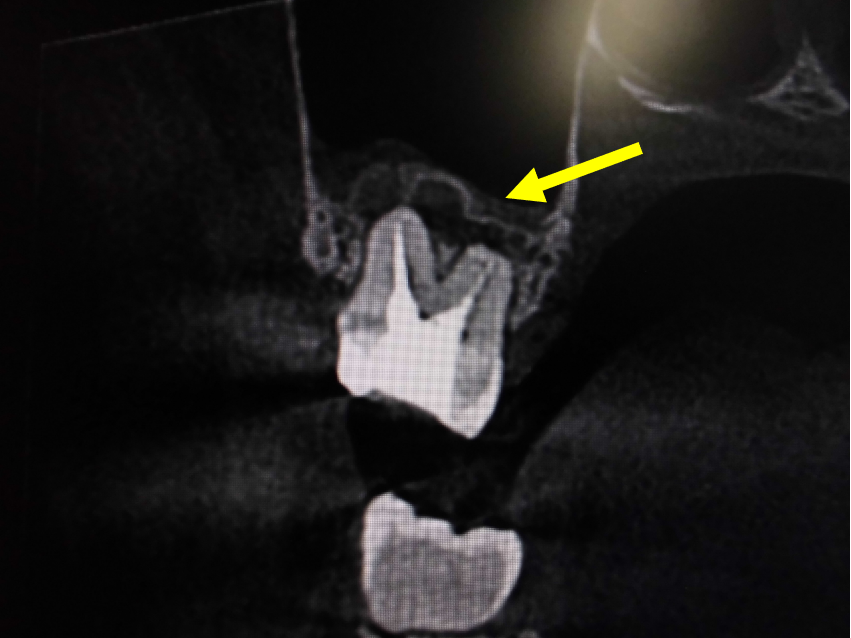

上顎洞との位置関係が確認できます。

CTでは近心の第二根管も確認できます。